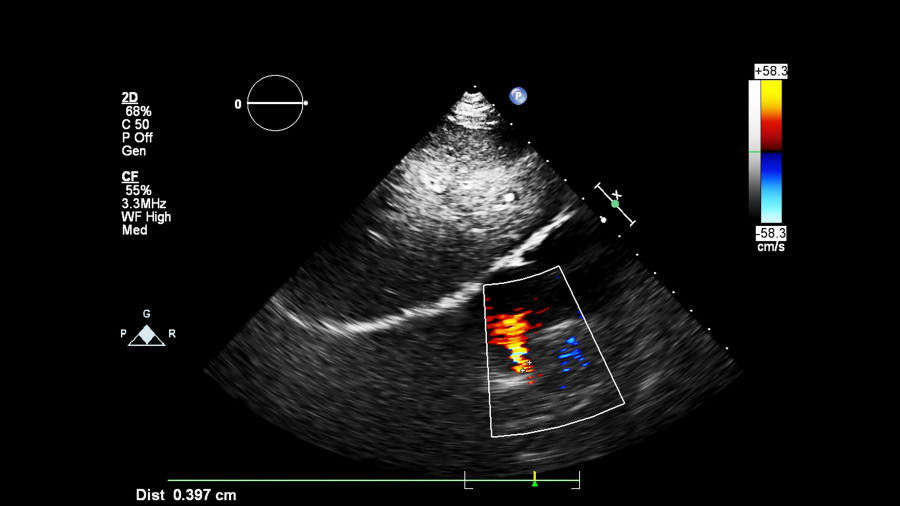

Κατά την 6η εβδομάδα της εγκυμοσύνης σχηματίζεται η πρώιμη καρδιά του εμβρύου, η οποία αρχίζει να πάλλεται και να κυκλοφορεί αίμα. Αυτοί οι πρώτοι παλμοί μπορούν να ανιχνευτούν κυρίως με υπερηχογραφικό έλεγχο δια της κολπικής οδού καθώς η μικρή μήτρα καλύπτεται από τα οστά της λεκάνης και οι υπέρηχοι δεν διαπερνούν εύκολα. Σε γυναίκες που δεν επιθυμούν κολπικό υπερηχογράφημα, συνήθως χρειάζεται να περιμένουν μέχρι την 7η ή 8η εβδομάδα, οπότε ο καρδιακός παλμός μπορεί να ακουστεί με κοιλιακό υπερηχογράφημα.

Το σωματικό λίπος μπορεί να εμποδίσει τη μετάδοση του ήχου, δυσκολεύοντας την ανίχνευση του καρδιακού παλμού. Σε αυτές τις περιπτώσεις, ο διακολπικός υπέρηχος ίσως βοηθήσει περισσότερο.

Ο τρόπος που είναι τοποθετημένη η μήτρα (π.χ. λυγισμένη προς τα πίσω) ή η θέση του πλακούντα μπορεί να επηρεάσει το πώς μεταδίδονται ήχος/σήματα.

Το υπερηχογράφημα Doppler στην εγκυμοσύνη: Όλα όσα πρέπει να γνωρίζετε